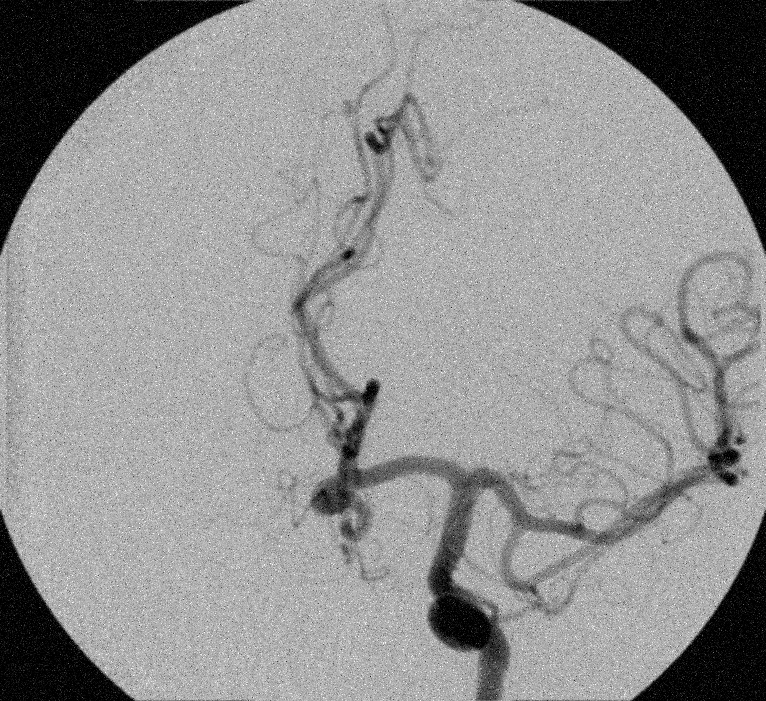

Example 2: restoration of images corrupted by blur and SPN or AWLN. In this example we evaluate the performance of the proposed TV-L1 model on three medical test images lungs (), Fig. 5 (a), ecography (), Fig. 6 (a), and aneurism (), Fig. 7 (a), synthetically corrupted by Gaussian blur of parameters band=5 and sigma=1 and by two types of impulsive noise, namely SPN and AWLN.

![]() |

| (a) original | (b) TV-L1 (ISNR = 18.55) | (c) zoom of (b) |

| (d) corrupted | (e) TVp-L1 (ISNR = 19.10) | (f) zoom of (e) |

| (g) -map () | (h) TV-L1 (ISNR = 21.14) | (i) zoom of (h) |

| (l) -map () | (m) TV-L1 (ISNR = 24.47) | (n) zoom of (m) |

First, for what concerns corruptions by SPN, in Figs. 5, 6, 7 we report for the three considered test images the original and corrupted image together with the estimated -maps in the first column (with the size of the neighborhoods used for the -maps estimation reported in the captions), the restoration results, obtained by the four compared methods, in the second column (with the achieved ISNR values in the captions) and a zoomed detail of the restored images - green- bordered in Figs. 5 (a), 6 (a), 7 (a) - in the last column.

The reported ISNR values as well as the visual inspection of the restored images and of the zoomed details strongly indicate how the proposed space-variant regularizer allows for higher quality restorations. In particular, it is worth remarking how, with respect to the space-variant TV model, the additional degrees of freedom represented by the scale parameters used in our proposal, yield a sufficient additional flexibility for avoiding unwanted spurious effects - see, e.g., spikes in Figs. 5 (i), 6 (i), 7 (i).